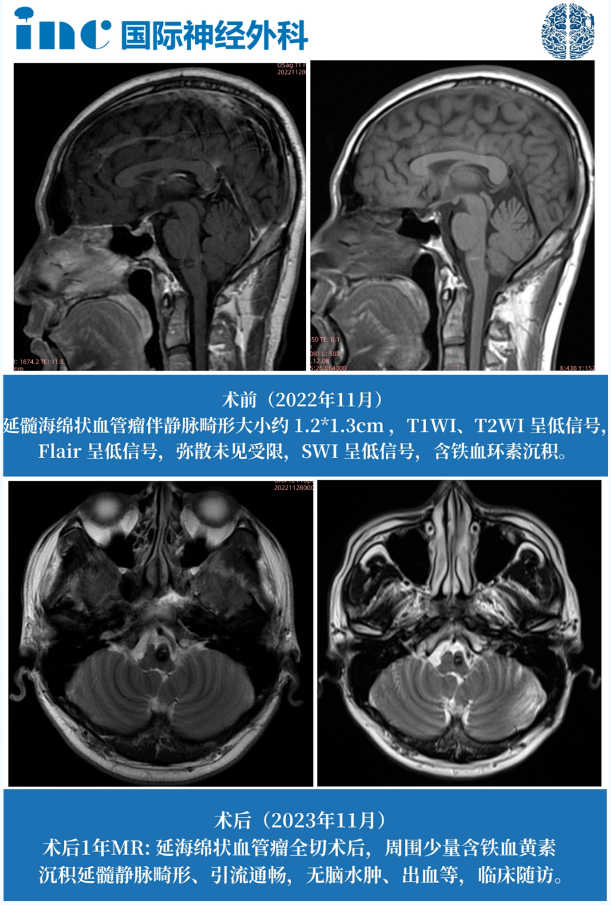

巴教授术后影像对比

巴教授术后1年随访影像对比